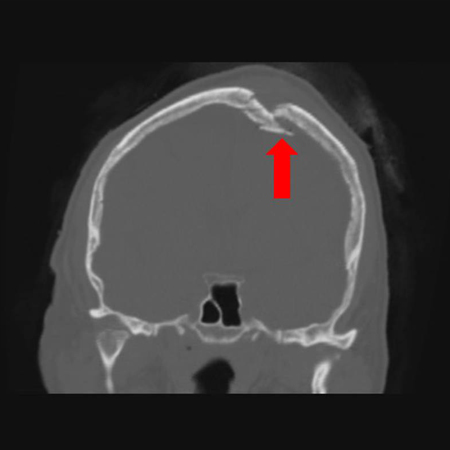

Coronal CT of an open, comminuted, depressed skull fracture. The level of depression is greater than the bony table and there are several bone fragments impacted below the inner cortex of the opposing bone (large arrow). Despite lack of underlying associated brain injury this fracture required operative debridement and elevation of the bone fragments. See also the corresponding sagittal CT image

From the teaching collection of Demetrios Demetriades; used with permission